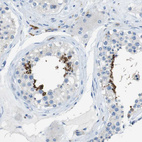

Immunohistochemistry analysis in human testis and skin tissues using HPA012634 antibody. Corresponding CLMN RNA-seq data are presented for the same tissues.